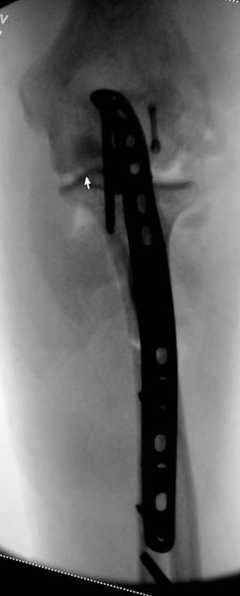

Снимки вот еще какие есть (наши лаборанты пытались сделать что то)

|

В начале недели видел снимок (больного -нет). Конечно, венечный отросток сломан. Сложности возникают из-за небольших размеров верхушки локтевого отростка и первичного дефекта. Не везде имеются специальные пластины. Мы обходимся обычной трубчатой пластиной + проволочная петля. Снимки, похожие, выложу позднее (необходимо отредактировать).

Здесь выставлены несколько случаев и варианты фиксации локтевого отростка, некоторые в комбинации с другими переломами.

1 вариант применен ACUMED локинг пластина

2 вариант

перелом локтевого отростка с переломом головки лучевой кости (использованы 2 мм шурупы)